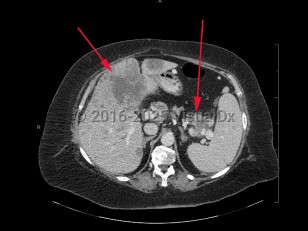

Metastatic pancreatic carcinomaMetastatic pancreatic carcinoma